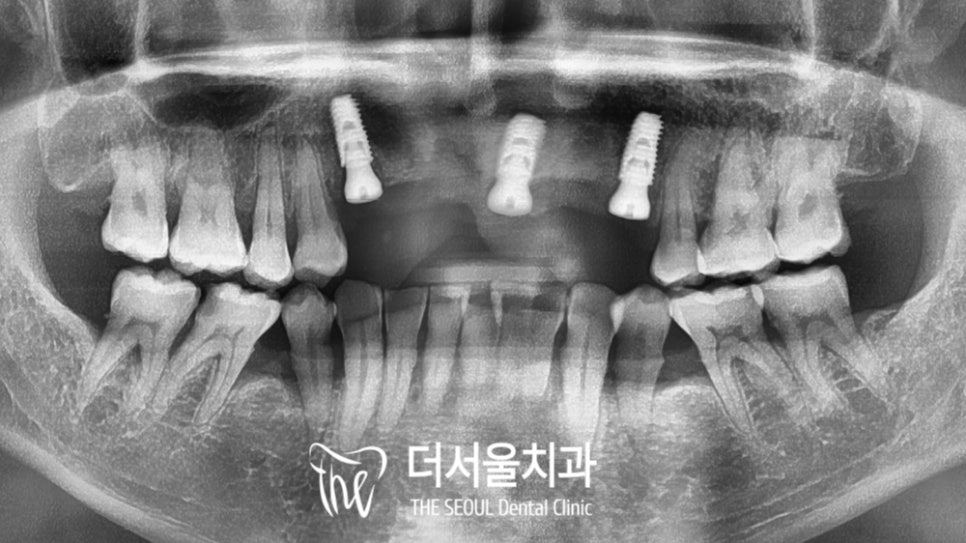

파노라마를 찍어 확인해 보니

이전에 신경치료를 받았던

흔적을 볼 수 있었는데요.

컴퓨터 분석을 사용하여

식립 위치를 계산했습니다.

전치부는 폭이 좁고

치조골이 충분하지 않기 때문에

이런 점을 모두 고려하여 픽스쳐의

종류를 결정할 수 있었는데요.

앞서 정해놨던 곳에

알맞게 심어진 고정체의 모습입니다.

다행히 초기 고정력도 어느 정도 잘 나왔으며

계획했던 곳에 잘 심어졌는데요.